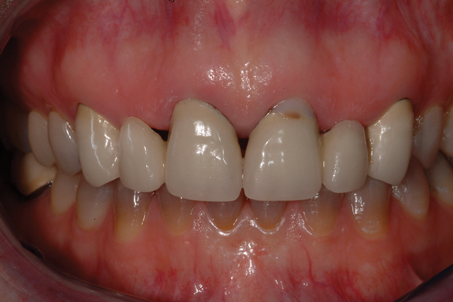

It is essential that an ovate pontic be convex in all dimensions. However, with the traditional "egg in the nest" shape, the gingival marginal tissue over the facial aspect of the pontic is commonly rolled rather than knife edged, which can result in a shadow (Figure 1) and give away that it is a pontic rather than a natural tooth. Therefore, the critical issue isn't the shape of the intaglio surface of the pontic but rather the emergence profile of the pontic on its facial surface. Where the facial aspect of an ovate pontic emerges from the soft tissue, it should have the same contour as a natural tooth. Therefore, it should not be rounded. The facial aspect of an ovate pontic should have a flat surface that goes approximately 1.0 mm under the gingival crest before it starts to become rounded (Figure 2). The shape of the rounded surface of the pontic is determined by the thickness of the ridge in the created site. It will be more round for a thick ridge and more pointed for a thin ridge.

(1.) The gingival marginal tissue over the facial aspect of an ovate pontic with an

Figure 1